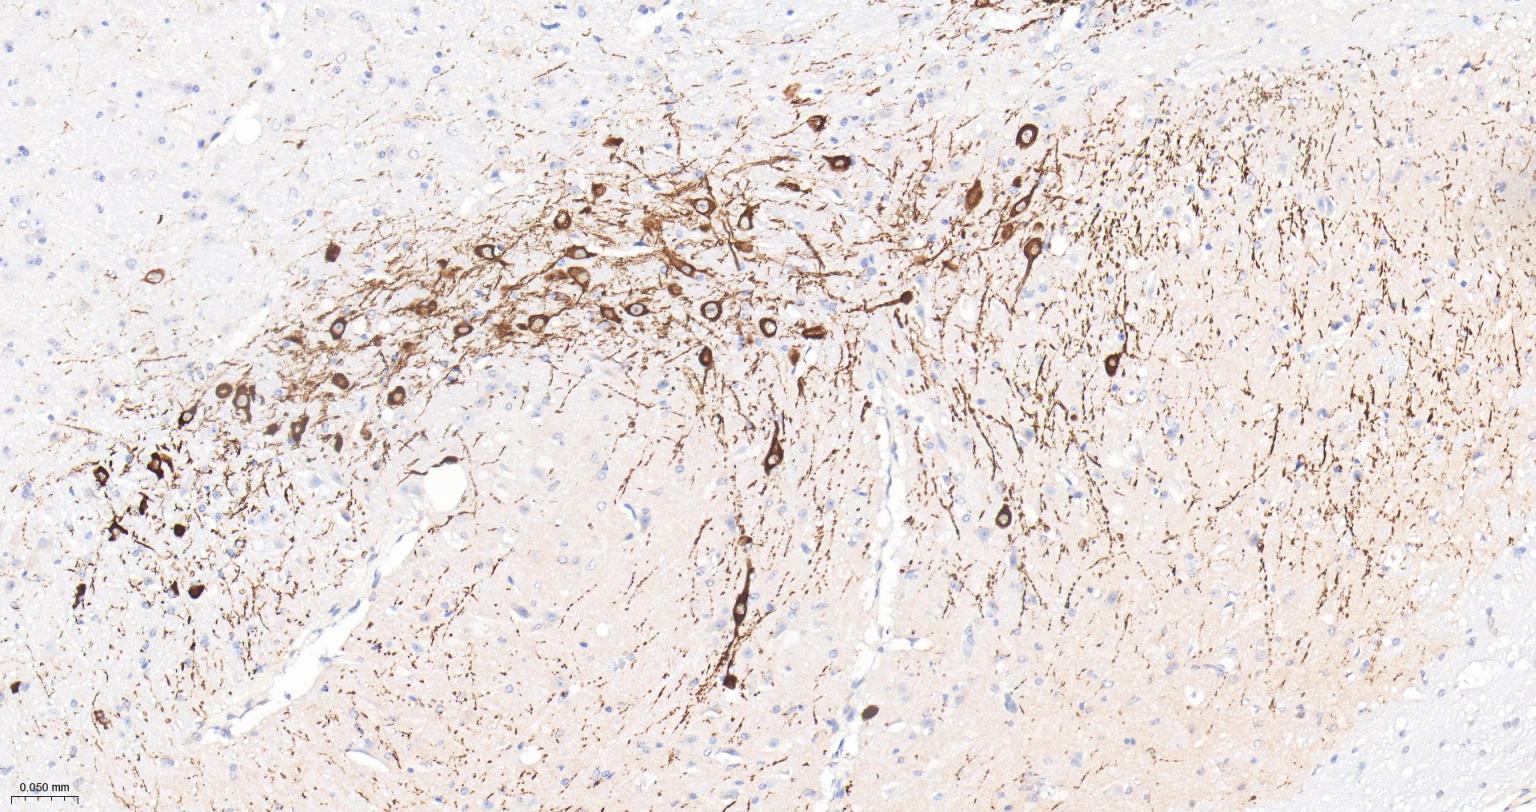

Paraformaldehyde-fixed, paraffin embedded Rat Cerebrum; Antigen retrieval by boiling in sodium citrate buffer (pH6.0) for 15 min; Antibody incubation with Tyrosine Hydroxylase Monoclonal Antibody, Unconjugated(bsm-52574R) at 1:200 overnight at 4°C, followed by conjugation to the bs-0295G-HRP and DAB (C-0010) staining.

Paraformaldehyde-fixed, paraffin embedded Mouse Cerebrum; Antigen retrieval by boiling in sodium citrate buffer (pH6.0) for 15 min; Antibody incubation with Tyrosine Hydroxylase Monoclonal Antibody, Unconjugated(bsm-52574R) at 1:200 overnight at 4°C, followed by conjugation to the bs-0295G-HRP and DAB (C-0010) staining.